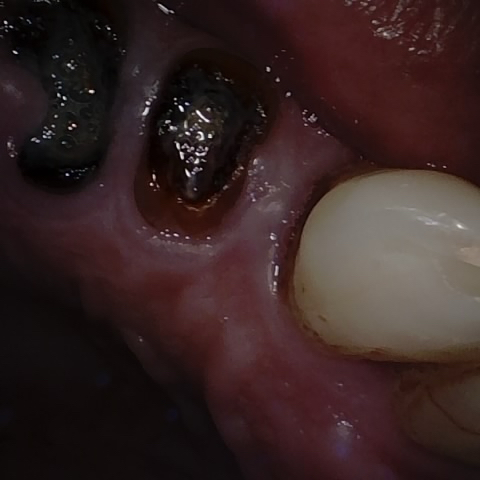

Incorrect Quality Level

The reference annotation for this image is

None

.

Please select the correct quality level.

Annotated as "Good"